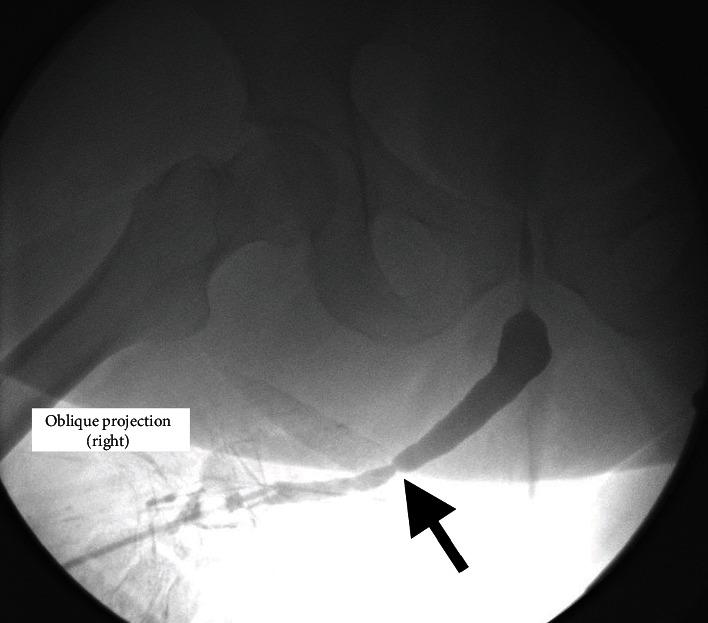

Hypospadias is a congenital malformation of the male lower urinary tract, consisting of a ventral urethral opening proximal to the glans penis. This condition is corrected surgically in the paediatric age, with a great variety of techniques available. Traditionally, a tubularized genital skin was used for one- or two-stage repairs. Nowadays, the tendency is to use preputial or oral mucosa grafts, dorsally located, to avoid diverticula formation and prevent hair growth in the neourethra. We present a case of a patient born with proximal hypospadias with penoscrotal transposition, surgically corrected in his childhood, using dorsal penile skin island flap. The patient is referred to urology consultation in his adulthood for a weak urinary stream, recurrent infections, and a large amount of hair exiting through the urethral meatus.

尿道下裂是男性下尿路的一种先天性畸形,表现为阴茎头近端的腹侧尿道开口。这种情况在儿童期通过手术矫正,有多种技术可供选择。传统上,管状化的生殖器皮肤用于一期或二期修复。如今,倾向于使用位于背侧的包皮或口腔黏膜移植物,以避免憩室形成并防止新尿道内毛发的生长。我们报告一例患有近端尿道下裂并伴有阴茎阴囊转位的患者,童年时通过手术使用阴茎背侧带蒂皮瓣矫正。该患者成年后因尿流无力、反复感染以及大量毛发从尿道口长出而转诊至泌尿外科会诊。